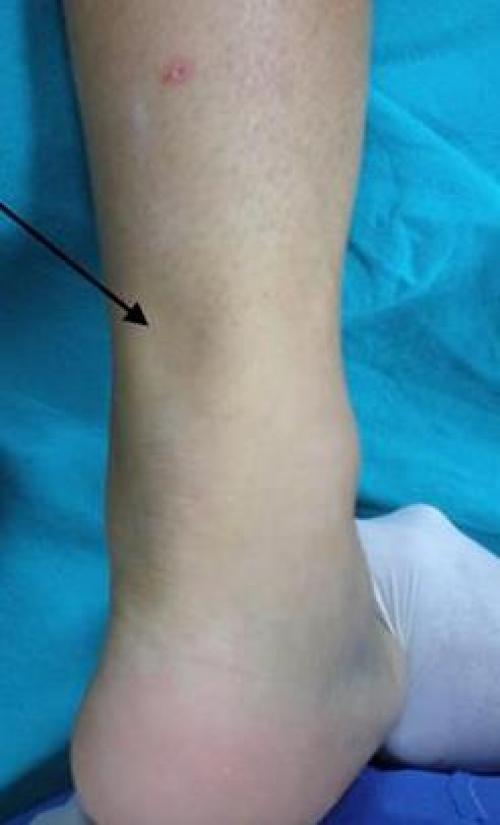

Повреждение ахиллова сухожилия проявляется резкой болью, напоминающей ощущения от удара или пореза, по задней поверхности голени чуть выше голеностопного сустава. При осмотре выявляется отек, болезненность при пальпации, западение на месте ахилла. Подошвенное сгибание стопы при полном разрыве невозможно, при частичном – ограничено. Опора существенно затруднена.

После сбора анамнеза с указанием типичного механизма травмы приступаем к осмотру. Помимо отёка и кровоподтёка важным диагностическим критерием является угол который расслабленная стопа принимает в положении сгибания в коленном суставе до 90 ° по сравнению со здоровой стороной. В норме этот угол составляет 15-25° и он одинаков с обеих сторон.

При пальпации часто удаётся обнаружить дефект, увеличивающийся при тыльном сгибании стопы.